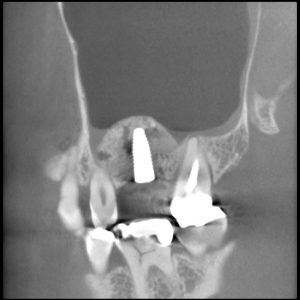

2016年6月にサイナスリフトをおこなった症例(30…

ストレスマネージメントとしての睡眠時のはぎしりは時として、咬合の崩壊をもたらします。 30代であれば、奥歯の再生とスムーズな歯ぎしりの誘導は、精神的にも全身の健康にも及ぼす効果は計り知れません。それほど奥歯の再生は重要です。 上あごの骨が無いところにインプラントを埋入しなければなりません。とる…